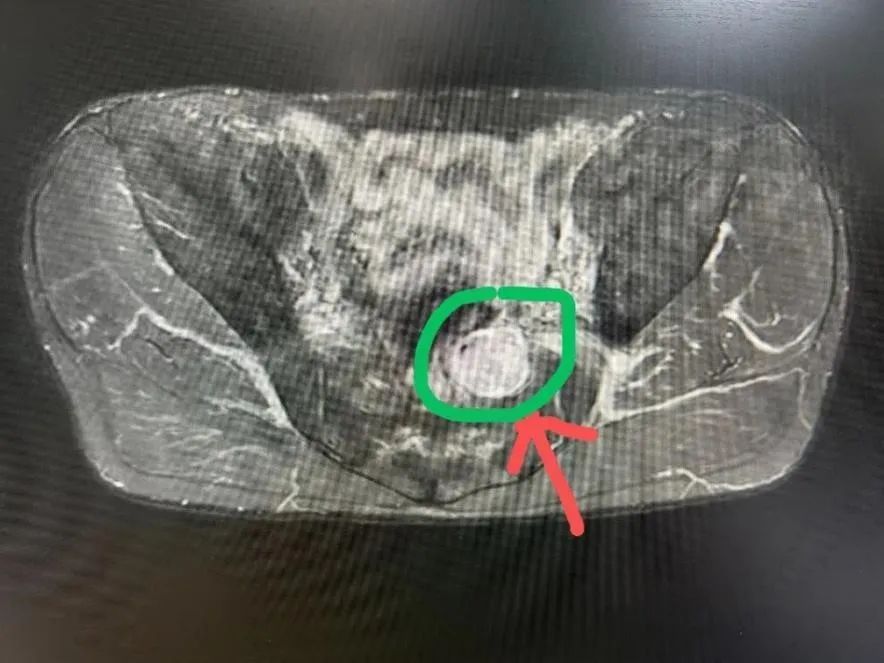

今年38岁的郑先生在体检时发现盆腔肿块,心急如焚的他前往上海市第六人民医院骨与软组织肿瘤诊治中心就诊。市六医院骨肿瘤科副主任医师张智长在完善影像学检查后发现,肿块起源于腹膜外骶2神经根,约4cm大小,考虑神经鞘瘤可能。由于肿瘤位置较深,周围解剖结构复杂,后方被骶骨阻挡,前方为腹腔,包括肠道、输尿管、膀胱等重要脏器,周围毗邻多条动脉、静脉血管,手术难度较大。